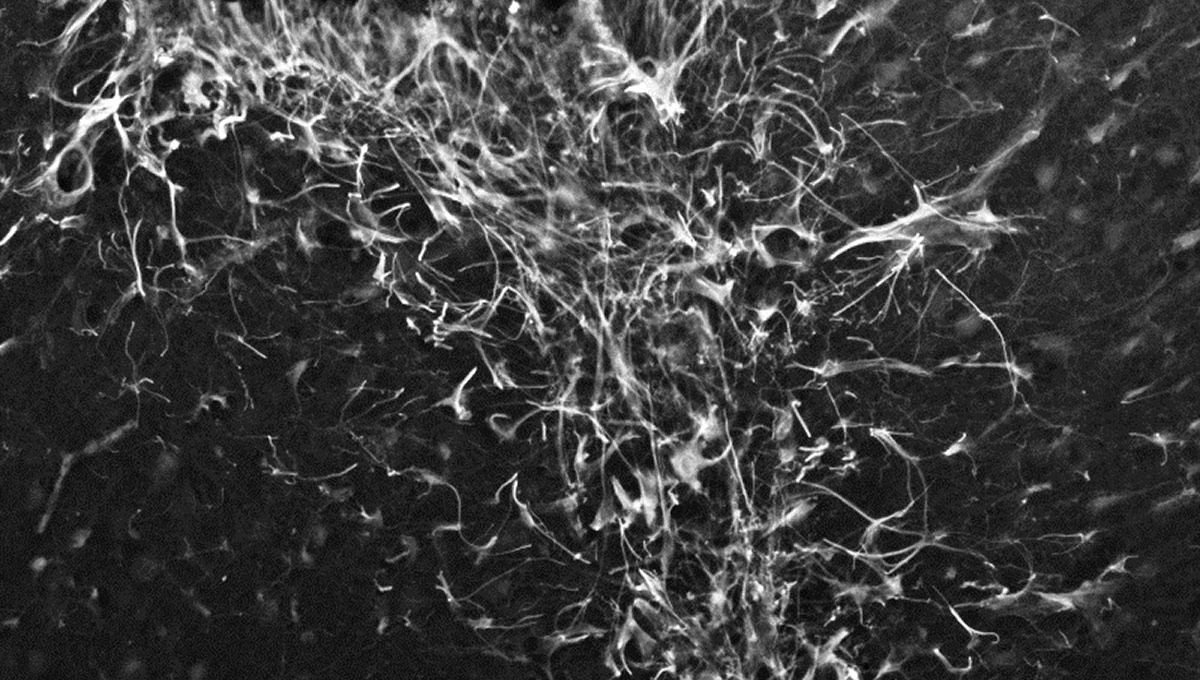

Although the exact cause of Parkinson’s is unknown, its onset is associated with a combination of environmental and genetic factors. In nearly every case, alpha-synuclein aggregates into clumps of spaghetti-like filaments that researchers believe somehow lead to decreases in dopamine and other changes in the body.

“Proteins bind together and form these stringy, fibrous fibrils. That is not good,” says Holahan. “That means they are starting to clump together. And somewhere along the line they start to spread. Little chunks break off and invade other neurons, which is how a lot of neurodegenerative diseases spread throughout the brain, kind of like how a virus would infect a person or population. That’s the problem we want to stop.”

The green microscope image featured above is from Matthew Holahan’s experiments and shows the accumulation of a protein called alpha-synuclein in a mouse brain; the bright spots show alpha-synuclein aggregating into clumps of spaghetti-like filaments that, researchers believe, lead to decreases in dopamine and Parkinson’s symptoms such as slow movements, tremors and rigidity. The red image shows A-syn-1, the aptamer Holahan and Maria DeRosa designed to target the protein. The yellow image shows the successful co-localization of A-syn-1 and alpha-synuclein, which has the potential to help stop Parkinson’s disease. The black-and-white images, in order of appearance from top to bottom, show: dopaminergic neurons in the substania nigra, part of the midbrain where Parkinson’s pathology occurs and affects motor function — dopaminergic neurons are the main source of dopamine in the brain; the motor cortex, where Holahan and DeRosa’s research is focused; and what neurodegeneration looks under a microscope.